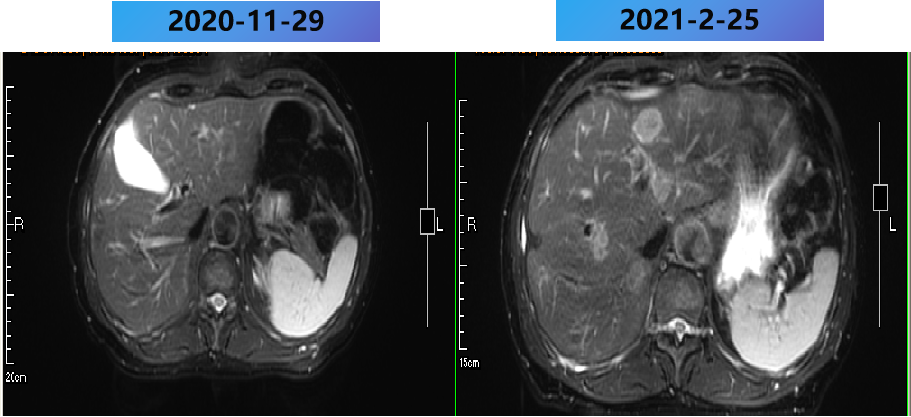

2019年11月7日 行PET-CT:

1. 乙状结肠部位高代谢病变,肝内多发高代谢灶,左肺上叶尖后段高代谢结节,以上均考虑恶性,乙状结肠癌伴左肺及肝脏转移可能性大。

右肺上叶局限性肺气肿改变;右肺门稍高代谢淋巴结,多考虑炎性反应淋巴结。

PET-CT影像

1、乙状结肠癌TXNXM1 IV期,多发肝转移,肺转移(孤立)。

基因检测:KRAS、NRAS、BRAFV600E未见突变,MSS。